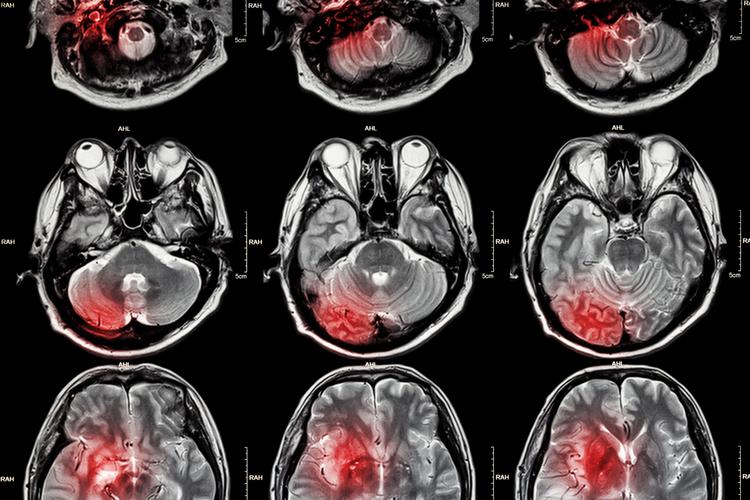

要理解一个基本背景:大脑是一个耗氧量极高的器官,它的血液供应必须非常充足和稳定,任何原因导致大脑局部区域的血液供应中断,都会造成脑组织缺血、缺氧,最终导致脑细胞(神经元)死亡。

“缺血灶”和“脑腔梗”都是脑组织曾经缺血坏死的“遗迹”或“疤痕”,它们在核磁共振(MRI)上表现为信号异常的区域,是医生判断脑血管健康状况的重要依据。

为什么会出现这些病灶?常见原因

这些病灶的出现,通常不是偶然的,是身体长期处于不健康状态的结果,主要与以下因素密切相关:

- 高血压:首要元凶,长期高血压会冲击、损伤细小的血管壁,导致动脉硬化、变性,最终堵塞。

- 心房颤动(房颤):心脏不规则跳动时,容易在心房形成血栓,血栓脱落随血流进入大脑,堵塞血管(这种通常引起较大面积的梗塞,但也可能引起小栓塞)。